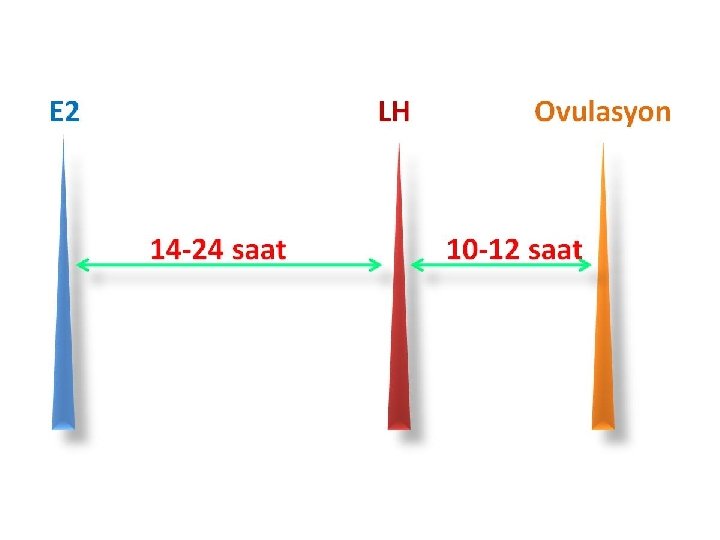

Positive feed back of E 2 more than 200 pg /ml > 50 hours

A threshold of LH 14 -27 hours for full maturation of the oocyte to occur